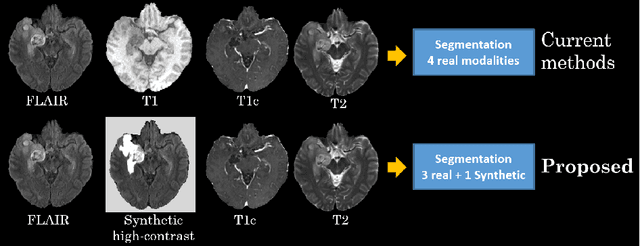

The magnetic resonance (MR) analysis of brain tumors is widely used for diagnosis and examination of tumor subregions. The overlapping area among the intensity distribution of healthy, enhancing, non-enhancing, and edema region makes the automatic segmentation a challenging task. Here, we show that a convolutional neural network trained on high-contrast images can transform intensity distribution of brain lesion in its internal subregions. Specifically, generative adversarial network (GAN) is extended to synthesize high-contrast images. A comparison of these synthetic images and real images of brain tumor tissue in MR scans showed significant segmentation improvement and decreased the number of real channels for segmentation. The synthetic images are used as a substitute for real channels and can bypass real modalities in the multimodal brain tumor segmentation framework. Segmentation results on BraTS 2019 dataset demonstrate that our proposed approach can efficiently segment the tumor areas.